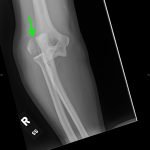

Lateral Epicondyle Fracture

Radiographs of the right elbow revealed an acute fracture through the lateral epicondyle with dislocation of the radial head inferiorly. Radiographs of the left elbow revealed a slightly angulated fracture through the lateral epicondyle.